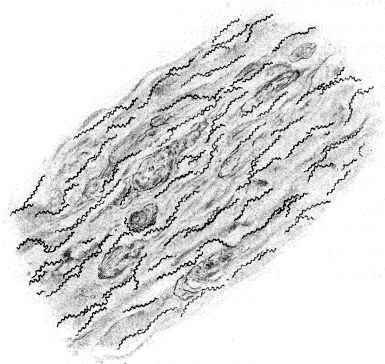

Ein halbes Jahrhundert später erst gelang es den geschickten Händen Antony van Leeuwenhoeks, kleine Linsen so sorgfältig und gleichmäßig zu schleifen, daß sie alle bis dahin angefertigten an Vergrößerungskraft übertrafen; er vervollkommnete hierdurch und durch kleine anderweitige Kunstgriffe seine optische Ausrüstung in bisher noch nicht dagewesenem Maße und untersuchte nun – von Haus aus ohne jede naturwissenschaftliche Ausbildung – mit ihrer Hilfe allerhand Flüssigkeiten: Regenwasser, Pflanzenaufgüsse, Darminhalt von Tieren und Menschen, den eigenen Speichel u. a. m. mikroskopisch.[3] Überall fand er – bald reichlicher, bald spärlicher – kleinste, vollkommen farblose »Tierchen«, die verschieden gestaltet, zum Teil lebhaft beweglich waren. Dank einer vorzüglichen Beobachtungsgabe und ebenso großer Zuverlässigkeit beschrieb Leeuwenhoek diese »Tierchen« so genau, daß wir sie heute mit Sicherheit als Bakterien wiedererkennen können. Auch gab er durchaus naturgetreue Abbildungen von ihnen, die die drei Hauptformen der Spaltpilze vollkommen richtig darstellen: alle die unzähligen Bakterien, die seitdem beobachtet worden sind, lassen sich ihrer Gestalt nach in kugelförmige (Mikrokokken), stäbchenförmige (Bazillen) und schraubenförmige (Spirillen) scheiden (s. Abb. 1). Freilich wechseln sie nach Dimensionen und kleinen Einzelheiten ihres Baues, wie wir sehen werden, in mannigfaltigster Weise, aber alle lassen sich auf einen der drei schon von Leeuwenhoek unterschiedenen Grundtypen zurückführen.

Sehr vieles sprach zugunsten der ersteren Anschauung; vor allem entsprach sie den Erfahrungen, die bei der Erforschung der lebenden Wesen unserer Erde bis dahin gesammelt waren. Der einwandfreie Nachweis ihrer Richtigkeit stieß aber auf eine sehr große Schwierigkeit: fast überall, wo wir in der Natur Bakterien in größeren Mengen begegnen, finden wir verschiedene, ja meist sogar sehr zahlreiche verschiedene Formen in buntem Durcheinander; z. B. treffen wir in einem Tröpfchen Zahnschleim regelmäßig kurze und lange, dünnere und dickere Stäbchen und Schrauben, daneben kleinere und größere[5] Kugelbakterien miteinander vermengt (vgl. Abb. 2). Es war so gut wie unmöglich, an solchen Bakteriengemischen einwandfreie Beobachtungen über die Fortpflanzungsweise der Bakterien zu machen. So ist es verständlich, daß über diese Frage die Ansichten lange Zeit auseinandergingen.

Bei einiger Übung werden wir aber bald erkennen, daß wir ein Kugelbakterium, ein Stäbchen- oder ein Schraubenbakterium vor uns haben. Mit wachsender Übung vermögen wir – unter Umständen auf den ersten Blick – besonders charakteristische Bakterienarten zu erkennen. Anderseits können wir bei sorgfältiger Beobachtung feine Unterschiede der Formen unter den Angehörigen der drei Grundtypen bald auffinden: so weichen z. B. manche Mikrokokken ein klein wenig von der Kugelgestalt ab, sie sind ein wenig abgeplattet; eine andere Art ist ein klein wenig längsoval, usf. Zur[13] Unterscheidung der Kugelbakterienarten, die im allgemeinen der Eigenbewegung ermangeln, kann uns auch die Art ihrer Lagebeziehungen im hängenden Tropfen wichtige Dienste leisten. Manche Arten bilden in einer Kultur regelmäßig perlschnurartige, kürzere oder längere, 3 bis 5, ja bis 30 und mehr einzelne Glieder aufweisende Ketten (Kettenkokken oder Streptokokken, vgl. Abb. 28, 29). Andere dagegen lagern sich zu weintraubenförmigen Häufchen zusammen und werden danach als Staphylokokken (ἡ σταφυλή die Weintraube) bezeichnet (vgl. Abb. 26). Zwischen den verschiedenen Arten der Stäbchen- und Schraubenbakterien bestehen ferner Unterschiede nach der Länge und Dicke und nach dem Verhältnis des Längen- zum Dickendurchmesser: so begegnen wir langen und schlanken, langen und plumpen, kurzen und schlanken, kurzen und plumpen Stäbchen- und Schraubenformen. Wenn wir sie genau betrachten, so können wir oft noch weitere feine Unterschiede zwischen den verschiedenen Arten erkennen: die einen besitzen abgerundete Enden, die anderen kantige, manche zeigen die Neigung, dadurch, daß mehrere Individuen aneinander haften, Fäden zu bilden, und so gibt es noch eine ganze Reihe feiner Gestaltmerkmale, die der sorgfältige Beobachter zu berücksichtigen hat.